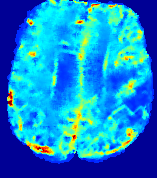

Slice #1Slice #2Slice #3Slice #4Slice #5Slice #6𝐕gt2subscriptnormsuperscript𝐕gt2\|{\bf{V}}^{\text{gt}}\|_{2}Refer to captionRefer to captionRefer to captionRefer to captionRefer to captionRefer to caption(a)Refer to captionRefer to captionRefer to captionRefer to captionRefer to captionRefer to caption(b)Refer to captionRefer to captionRefer to captionRefer to captionRefer to captionRefer to caption(c)Refer to captionRefer to captionRefer to captionRefer to captionRefer to captionRefer to caption(d)Refer to captionRefer to captionRefer to captionRefer to captionRefer to captionRefer to caption(e)Refer to captionRefer to captionRefer to captionRefer to captionRefer to captionRefer to caption(f)Refer to captionRefer to captionRefer to captionRefer to captionRefer to captionRefer to captionRefer to caption000.30.30.30.60.60.60.90.90.91.21.21.21.51.51.5(mm/s)𝑚𝑚𝑠(mm/s)

Figure 12: PIANO effectiveness and robustness testing: advection imaging via advection. Top row shows the ground truth 𝐕gt2subscriptnormsuperscript𝐕gt2\|{\bf{V}}^{\text{gt}}\|_{2} used for simulating pure advection. (a)-(f) refer to the results for 𝐕2subscriptnorm𝐕2\|{\bf{V}}\|_{2} estimated by PIANO, with simulated advection imaging series where Rician noise at levels 0%, 2%, 4%, 6%, 8%, 10% was added respectively.

Our goal here is to determine if PIANO can estimate a known velocity field from a concentration time-series consistent with this velocity field. To this end, for each patient in the ISLES 2017 training set, we treat the velocity field estimated by PIANO as the ground truth velocity field (𝐕gtsuperscript𝐕gt{\bf{V^{\text{gt}}}}), and the first image in the concentration time-series dataset {Cti}superscript𝐶subscript𝑡𝑖\{C^{t_{i}}\} (as described in Sec. 3) is used as the initial condition (C0superscript𝐶0C^{0}). We then simulate ‘advection imaging’ {Cti(Ω)|i=0, 1,, 40}conditional-setsuperscript𝐶subscript𝑡𝑖Ω𝑖0140\{C^{t_{i}}\in\mathbb{R}(\Omega)|i=0,\,1,\,\ldots,\,40\}, i.e., we create a time-series of concentration images driven by the velocity 𝐕:=𝐕gtassign𝐕superscript𝐕gt{\bf{V}}:={\bf{V^{\text{gt}}}} only via the advection PDE:

We further simulate noisy concentrations by adding Rician noise [24] with variances equalling 2%, 4%, 6%, 8%, 10% of the originally simulated concentrations {Cti}superscript𝐶subscript𝑡𝑖\{C^{t_{i}}\}. We then test how well PIANO can estimate the underlying velocity field via Eq. 15 with the same model settings (except without estimating the diffusion) as in Sec. 3 given the original and the noisy concentration time-series. Fig. 12 shows the estimated 𝐕est2subscriptnormsuperscript𝐕est2\|{\bf{V}}^{\text{est}}\|_{2} for one patient. Fig. 11 (a) shows the summarized estimation results for all 43 patients. PIANO almost perfectly captures the underlying velocity field, and maintains excellent performance even when estimating from concentrations with varying noise levels.